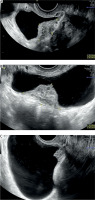

Endometriosis is a common gynaecological disease, which affects 10–15% of women in reproductive age. It is defined as the presence of functional endometrial foci outside the uterine cavity. Patients can experience a variety of nonspecific symptoms, but the most common are pain and infertility. Apart from this, endometriosis may present with haematuria, fatigue, painful rectal bleeding and metabolic and psychiatric disorders such as hypoglycaemia, depression, or anxiety [1–3]. Female infertility can be caused by different mechanisms such as fallopian tube destruction, chronic pelvic inflammation, changes in the immune system functions, and altered hormonal balance. Furthermore, inflammatory cytokines and cells affect eutopic endometrium, causing an implantation failure [1, 4]. Endometriosis is divided into three types: ovarian endometriosis, superficial (peritoneal) endometriosis, and deep endometriosis (DE) [1]. Deep endometriosis is defined as endometriosis invading pelvic organs more than 5 mm beneath their surface. One of the rare forms of endometriosis is urinary tract endometriosis (UTE), which can either occur as deep or superficial endometriosis. Urinary tract endometriosis affects 0.3–12% of women with endometriosis and this condition refers to/occurs in 20–52.6% of patients with DE [3, 5]. The most common location of UTE is the bladder, while the most dangerous type of UTE is ureteral endometriosis, because it can lead to silent and irreversible kidney damage. Bladder endometriosis (BE) is defined as the presence of endometrial foci in the vesical detrusor muscle (Figure 1). Bladder endometriosis most commonly affects the base and dome of the bladder [3]. The vesicouterine pouch or anterior cul-de-sac is also a common site of endometriotic involvement. Either peritoneal or deep endometriotic implants involving the serosal surface of the uterus often determine adhesions between the peritoneal folds of the bladder dome and the uterus with anteflexion of the uterus and obliteration of the anterior cul-de-sac. Bladder endometriosis was described for the first time in 1921 by Judd [6]. Since then, numerous case reports and research studies have been published regarding this topic. Despite the wide literature, the pathogenesis of BE is still unclear. Most popular theories explaining the pathogenesis of BE are retrograde menstruation, coelomic metaplasia, and the spread of stem/progenitor cells [3, 7]. At the moment, retrograde menstruation theory is considered to be the most explanatory. This theory states that menstruation blood with functional endometrial cells flows to the pelvic cavity through the fallopian tube orifices [1, 8]. Endometrial cells adhere to the peritoneum and start the inflammation facilitating the vesicouterine pouch endometriosis (EVUP) development and bladder infiltration. Novellas et al. have found that the endometrial cells implant to the outer layers of the bladder and later infiltrate the inner layers [9]. On the other hand, the retrograde menstruation hypothesis cannot explain the isolated BE form, in which case other theories seem to be more suitable. In addition, BE may be of iatrogenic origin, such as a consequence of bladder destruction during caesarean section (CS) [3, 7]. Bladder endometriosis presents a range of nonspecific symptoms such as urinary bladder pain, cyclic or noncyclic pelvic pain, dysuria, dyspareunia, increased urinary frequency, urinary incontinence, haematuria, and elevated intravesical pressure. Thus, the differential diagnosis of BE is challenging considering various mimicking diseases such as urinary tract infections, interstitial cystitis, bladder stones, and carcinoma [3, 7, 10]. As a chronic inflammatory disease, endometriosis can also have an impact on mental health, sleep quality, and life quality in general. The sleep and life quality of patients suffering from endometriosis is poorer than in healthy women. The main cause of sleep disturbances is pain and nocturia, but some researchers indicate that sleep insufficiency can in turn increase inflammation processes and worsen the pain. A similar pathophysiological mechanism can cause psychiatric disorders [11]. The most frequently used imaging modality in BE and EVUP is transvaginal ultrasonography (TVS) (Figure 2). Besides TVS, magnetic resonance imaging (MRI), transabdominal ultrasonography (US), or cystourethroscopy are used as supplementary imaging methods for those conditions [3, 10]. Surgical resection of endometrial foci is a gold standard therapy, which enables/makes it possible to completely treat the disease [3, 7, 12]. Surgical removal may be done by laparotomy, laparoscopy, or using a surgical robot. Apart from surgical resection, pharmacotherapy plays a key role in BE, leading to clinical improvement [3, 7]. Several treatment options such as progesterone-based therapy, combined oral contraception, and GnRH analogues are available. In our study we have decided to analyse the variety of symptoms and the outcomes of laparoscopic surgery done on BE and EVUP patients.

Numerous analyses of DE imaging methods are available in the literature. Guerriero et al. performed a systematic review with patients who underwent TVS before surgery, showing sensitivity of 62% and specificity of 100% for this diagnostic method [20]. Transvaginal ultrasonography is a reliable first-line imaging modality for the diagnosis of endometriosis involving uterosacral ligaments, rectovaginal septum, vagina, and bladder, particularly in patients with controlled pain and absence of intestinal stenosis or ureteral involvement [21]. Transvaginal ultrasonography can also be used for the follow-up of patients with ultrasonographic diagnosis of DE, whose symptoms have subsided during the medical treatment, or for those trying to become pregnant [20]. Holland et al. proved that the location of endometriosis lesions affect the diagnostic accuracy of TVS, obtaining the sensitivity and specificity of 100% for patients with BE, and only 16.7% sensitivity for patients with EVUP (specificity remained at 100%) [17]. High accuracy of the US in diagnosing BE was also shown in several other studies [22, 23]. In order to assess the extent of the endometriosis lesions in more detail, MRI can be chosen as a supplementary imaging modality. It is characterized by high accuracy for detecting endometriosis lesions and particularly foci hidden beneath healthy tissue or obliterated Douglas pouch [24].